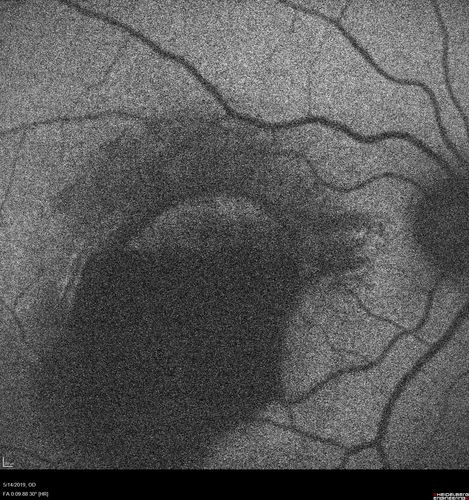

Macroaneurysm - Macular Hemorrhage - Branch Retinal Aterial Occlusion

62 year old African American female with chronic hypertension and vision loss for 2 weeks. VA is 20/400

Macroaneurym - Fresh Macular Hemorrhage - branch retinal arterial occulsion distal to MA